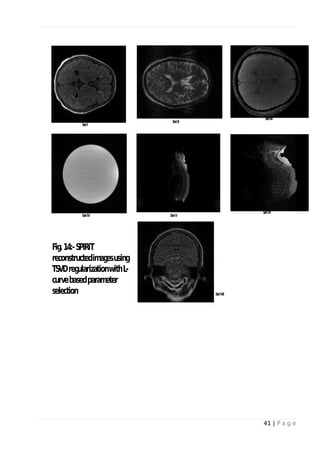

 L-curve method for selecting truncation parameter in TSVD:

Calibration matrix is constructed using both acquired and non-acquired samples within ACS. The

resulting L-curves are shown in Fig-9 and Fig-13. The circles indicate values of regularization

parameter at each point on the L-curve. Image reconstructed using the parameter values are shown

in Fig-10 and Fig-14. The residual aliasing in Data Set V and VI is evident. Data sets II, III, VII

shows sharp l-curve. All other data sets show similar performance as GRAPPA.

Fig. 14: - SPIRiT reconstructed images using TSVD regularization with L-curve based

parameter selection